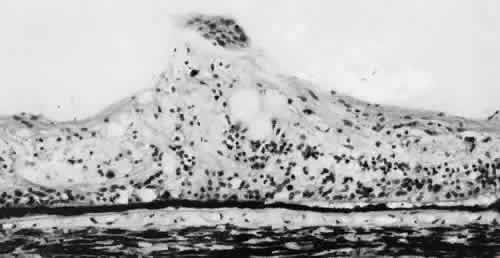

meridian (Fig. 9). The large dentate process and meridional fold are composed of excessive, disorganized, somewhat degenerated retinal tissue (Fig. 10).  Fig. 9. Meridional complex (arrow). Note its basic constituent, an atypical dentate process, which aligns

with and extends to an enlarged ciliary process. Complex also has a

meridional fold which extends along the dentate process and posteriorly

into the peripheral retina. Fig. 9. Meridional complex (arrow). Note its basic constituent, an atypical dentate process, which aligns

with and extends to an enlarged ciliary process. Complex also has a

meridional fold which extends along the dentate process and posteriorly

into the peripheral retina.

Fig. 10. Microsection of meridional complex through atypical dentate process and

its meridional fold. Anteriorly (on the left) the complex shows marked

redundancy of pigmented epithelium in its outer aspect and a dense glial

plaque on its inner aspect. Posteriorly (on the right) there is microcystoid

change, nonspecific degeneration, and dense-staining glial

cells along its surface. (Hematoxylin-eosin; × 63.) Fig. 10. Microsection of meridional complex through atypical dentate process and

its meridional fold. Anteriorly (on the left) the complex shows marked

redundancy of pigmented epithelium in its outer aspect and a dense glial

plaque on its inner aspect. Posteriorly (on the right) there is microcystoid

change, nonspecific degeneration, and dense-staining glial

cells along its surface. (Hematoxylin-eosin; × 63.)